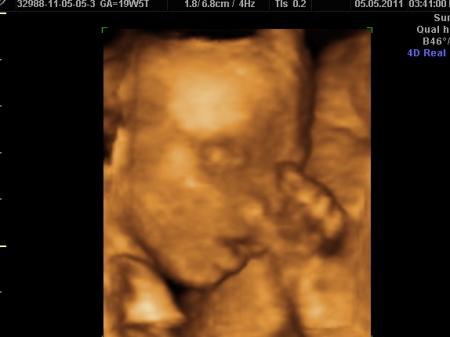

... Gesichtchen ... er hat seine Nase mit der linken Hand festgehalten..

Bild zu